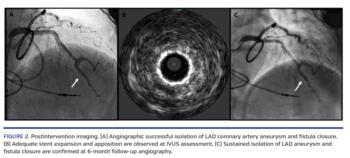

A 62-year-old female patient with refractory exercise intolerance was diagnosed with a large coronary-to-cardiac chamber fistula and coronary aneurysm developed within the first year post heart transplantation (Figure 1). Under intravascular ultrasound guidance, two polyurethane membrane-covered PK Papyrus stents (Biotronik) were implanted in overlap at mid left anterior descending (LAD) coronary artery segment. After postdilation, optimal stent expansion, aneurysm exclusion, and closure of the LAD fistula to the right ventricle were achieved (Figure 2). Mean right atrial pressure decreased by 30%, from 12 mm Hg before procedure to 8 mm Hg after percutaneous coronary intervention. At 6-month surveillance, coronary angiography, sustained fistula closure, and aneurysm exclusion were observed (Figure 2).